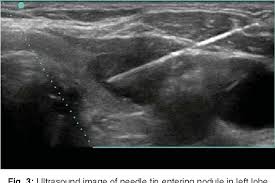

FNAC is a test used to check lumps or swellings in the body. A doctor uses a very thin needle to take a small sample of cells from a nodule or tumor. The sample is looked at under a microscope to check if the cells are normal or cancerous. Ultrasound Guided FNAC uses ultrasound images to help guide the needle, making sure the diagnosis of thyroid conditions like nodules, goiters, hyperthyroidism, and thyroid cancer is accurate. Medifyhome collaborates with NABL and NABH-accredited diagnostic centres, offering high-quality care at affordable prices.